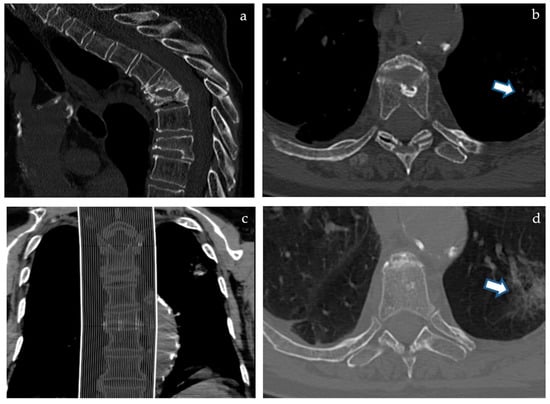

Figure 1. (a) (above left), (b) (above right), (c) (below left), and (d) (below right). A 77-year-old female patient with unbearable pain due to T5 and T6 spontaneous severe fractures (a,c) performed CT among a different institution due to the scarce compliance required for Magnetic Resonance. While reviewing CT imaging in our Interventional Radiology consultation office to assess the indication for vertebroplasty, a left lung opacity was noticed on “bone window” (b, arrow) and was confirmed and more evident when switching to “lung window” view mode (d, arrow).